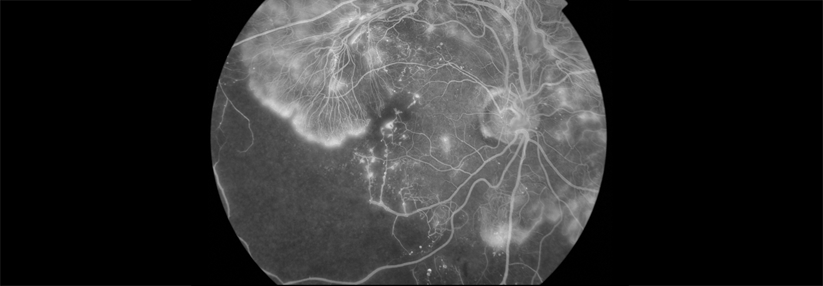

Künstliche Intelligenz erkennt Retinopathie

Die Retinopathie als häufige Folge des Diabetes kann dank der Technik nun leichter entdeckt werden.

Eine automatisiertes Verfahren verspricht das akkurate und schnelle Screening auf diabetische Retinopathie – ohne die Expertise eines Fachkollegen. Hausärzte können das KI-gestützte System nutzen, um Patienten in nur 60 Sekunden auf die Diabetesspätfolge zu untersuchen, heißt es in einer Pressemitteilung. Der Algorithmus konnte in einer kürzlich durchgeführten Studie bei 95,5 % der Betroffenen die Retinopathie korrekt erkennen (Sensitivität). Die Spezifität des Systems betrug 86 %.

Für die Untersuchung waren 893 Diabetiker mit dem System begutachtet worden. Nur in wenigen Fällen mussten die Pupillen der Patienten geweitet werden. Um die Ergebnisse zu validieren, wurde jeder Befund anschließend von einem Ophthalmologen überprüft.